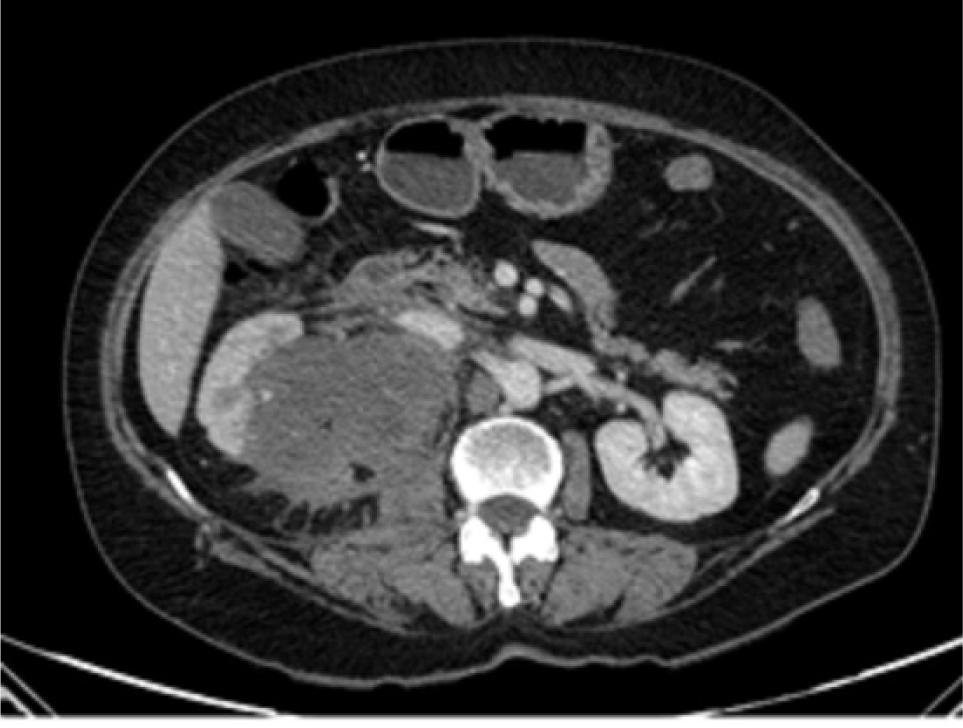

Postoperatively, the patient showed unremarkable recovery. Two months after surgery, the patient received chemotherapy (Adriamycin, Ifosfamide, and Vincristine) and radiotherapy, but an abdominopelvic CT scan showed widespread liver metastasis and local recurrence (Figure 4). The patient’s general condition worsened, and she passed away 5 months later.

Figure 4: Postoperative abdominopelvic CT scan demonstrates local recurrence and liver metastasis (Arrow).